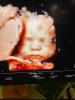

jabk0va wrote:Jakie piękne zdjęcie!! 😍😍😍

Śliczna buźka 🤩

2 miesiące i troszkę i już będzie z Wami ☺️

Moja pani doktor uwielbia wykorzystywać okazje do sesji jak tylko dziecko jest ładnie ułożone 🤭🥰